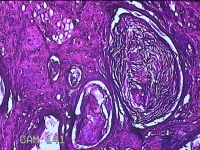

性别

男

年龄

47岁

临床诊断

皮脂腺囊肿

发现下颌部包块3年余,无疼痛及不适。

下颌部包块

大体所见

灰白暗红色带皮肤结节1.5x1.3x0.8cm一个,表面糜烂,切开结节呈实性,切面灰白粉红色,质软。

图2